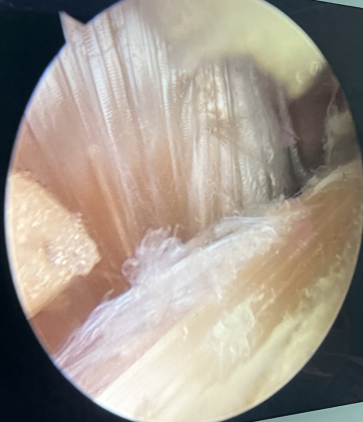

骨伤中心关节-运动科徐驰主任带领团队经过充分的术前准备,由刘志强、冯超医生择期为李女士在关节镜下行左膝关节镜下前、后交叉韧带重建+内侧副韧带修复+半月板修整成形术。

▲术中精细操作,重建膝关节功能

手术过程顺利,术后患者恢复良好,膝关节功能明显改善,膝关节稳定完全恢复,同时微创术后患者恢复快,术后第二天就能指导患者进行屈伸活动、肌肉力量等方面康复训练,手术取得了满意的效果。